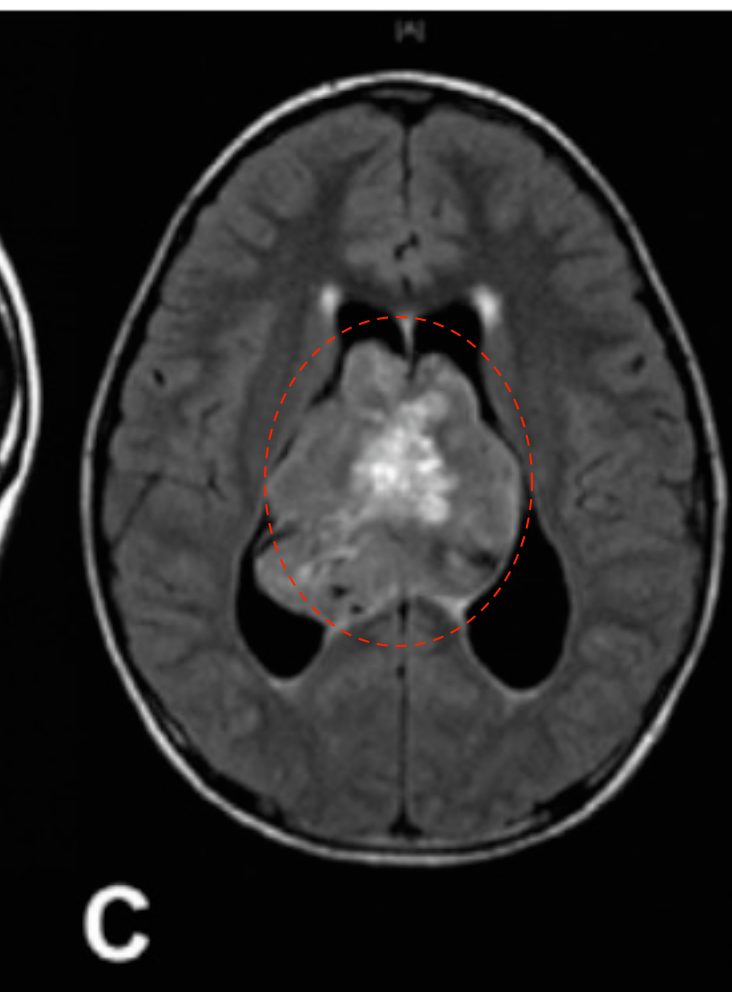

12岁男孩,因出现近3周的头痛和急性恶化而入院治疗。

(B & C)磁共振成像显示一个可能起源于透明隔的异质性强化肿瘤,填充在侧脑室和第三脑室的大部分区域。